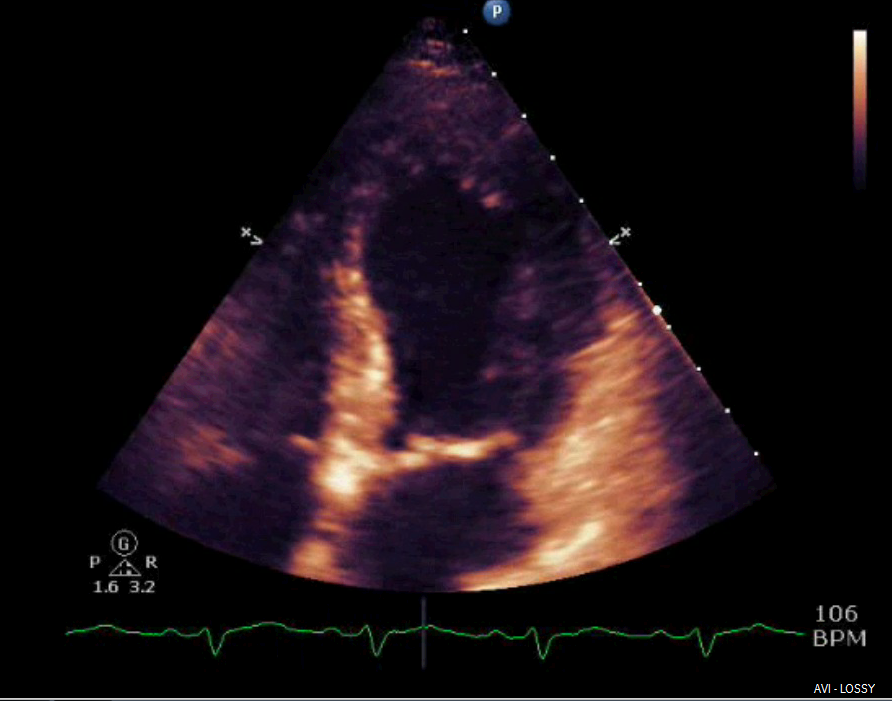

Neurogenic stunned myocardium is a triad of reversible left ventricular dysfunction, electrocardiogram changes and elevation of cardiac enzymes. Clinically, this provides diagnostic challenges in the setting of subarachnoid hemorrhage (SAH) due to the diagnostic uncertainty. The pathophysiological mechanisms for neurogenic stunned myocardium have included hypothalamic and myocardial perivascular lesions. More recently, alternative research has focused on myocardial microvascular dysfunction and genetic polymorphisms. Management has remained largely supportive with case reports citing the benefits of inotropes and intra-aortic balloon pumps in the setting of cardiogenic shock complicating NSM. When NSM follows SAH there are numerous complications, including pulmonary edema, arrhythmias and prolonged intubation, which can impact outcomes and increase morbidity and mortality. This highlights the need for accurate and timely diagnosis of NSM which has remained a clinical challenge. We report a case of a 52-year-old patient who presented to the ICU with complaints of atypical chest pain without neurologic complaints or lateralizing symptoms. She was admitted to the ICU for ongoing chest pain with concurrent ECG T-wave inversions. Within 24 hours she developed lateralizing neurologic signs and altered mental status with subsequent imaging revealing evidence of a SAH. We describe characteristics and outcomes of NSM in this patient with aneurysmal associated SAH.References